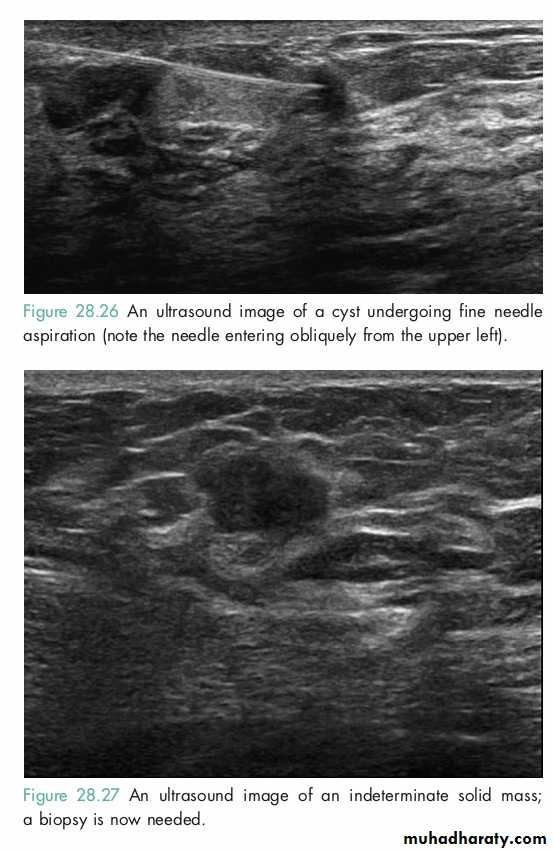

Ultrasound is particularly useful in young women with dense breasts in whom mammograms are difficult to interpret, and in distinguishing cysts from solid lesions.

FNA

TRUE CUT BIOPSY

It is easily performed, is rapid, inexpensive, and no incision is required.

It requires a trained cytopathologist to report.

Cannot distinguish between in situ and invasive cancer.Markers (ER, PR, Her-2-neu) are not routinely available.

This also does not need any incision, and can be read by any cytopathologist with basic training.Markers can be performed on this specimen.

It reliably distinguishes in situ and invasive carcinoma.Technique of choice in patients who are planned to receive preoperative systemic therapy.